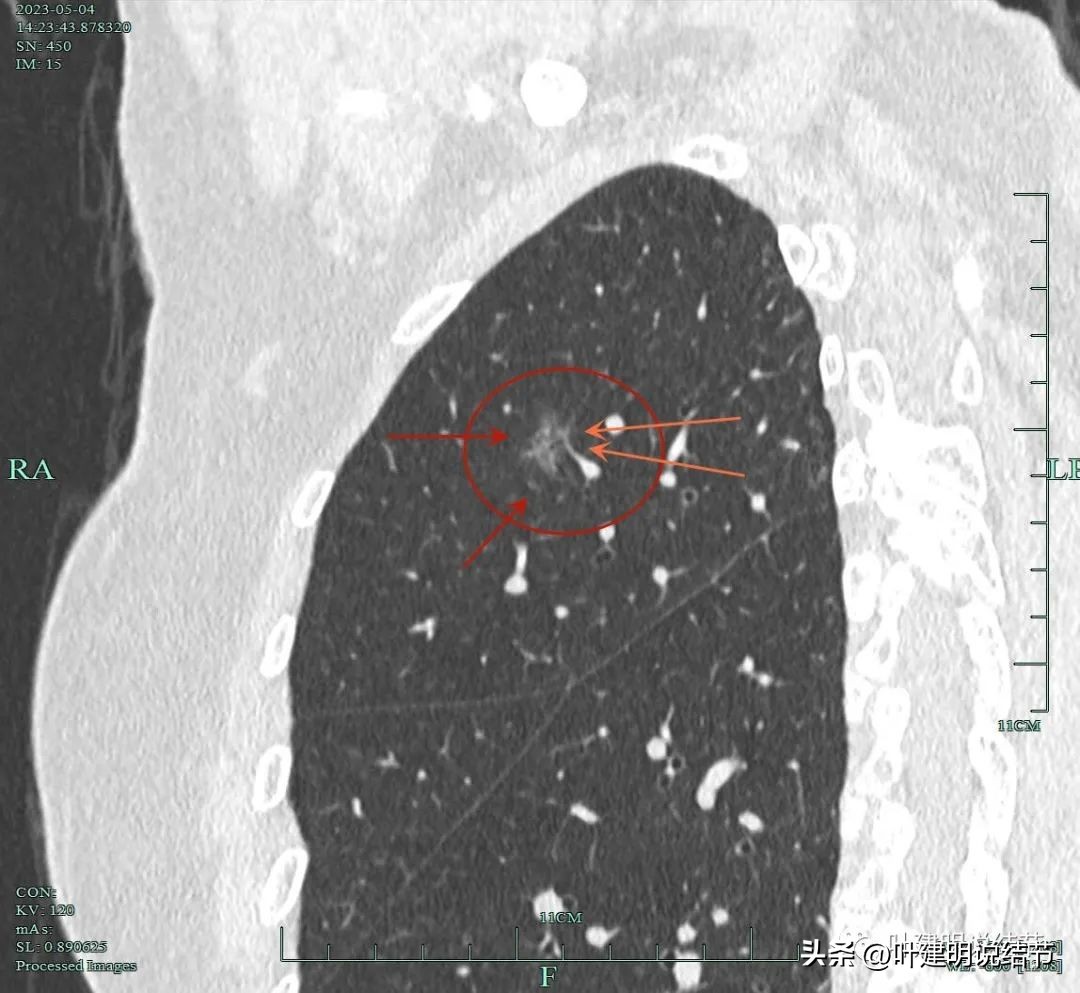

靶扫描重建发现病灶内部穿行血管毛糙,细支气管扩张,边缘毛刺样征。

灶内走行的血管模糊、异常增粗与毛糙。病灶总体轮廓较清,磨玻璃部分密度较低。

上图显示明显的血管弯征。而且磨玻璃病灶密度欠均匀。

病灶分叶、细支气管扩张,微小血管进入;整体轮廓较清。

上图这个视角清楚显示灶内的空泡征是扩张的细支气管。而且灶外细些,灶内更远离肺门,反而扩张,说明病灶有牵拉力呀!

边缘有毛刺征,灶内密度欠均。